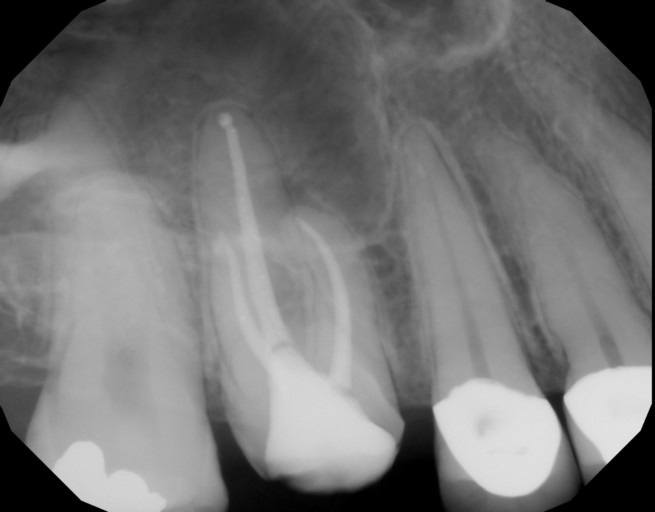

My tooth has an abscess so an endodontist started my root canal, drained it and put antibiotic inside and a temporary filling. When I went back to finish it he said it was still draining and I clearly still had the abscess on my gums but went on to seal the root anyway. Should he have better cleared the infection before finishing the procedure?

My tooth has an abscess so an endodontist started my root canal, drained it and put antibiotic inside and a temporary filling. When I went back to finish it he said it was still draining and I clearly still had the abscess on my gums but went on to...